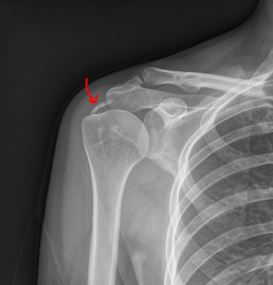

典型病例: 中年女性,突发肩关节疼痛,疼痛难忍,口服止痛药物效果不佳,外院就诊考虑“肩周炎”,予以被动活动锻炼等治疗,反而症状越来越重。

X线提示:肱骨头上方钙化灶

通过X线 /CT/MRI可以很容易诊断为肩袖钙化性肌腱炎,并通过关节镜微创手术,得到了根治!